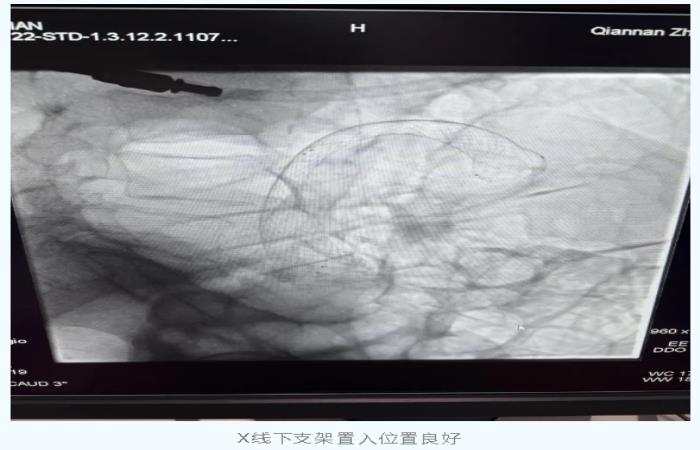

近日,我院收治了一名84岁降结肠癌术后复发伴肠梗阻的高龄患者,该患者多年前曾行降结肠癌根治术,近期出现腹痛腹胀、排便困难等症状,经检查确诊为肿瘤复发导致肠腔狭窄。在广州医科大学附属中医医院詹原泉主任医师(现任黔南州中医医院脾胃肝胆内科执行主任)的带领下,考虑到患者高龄、心肺功能差,传统二次手术风险极高,最终决定采用微创手术——“肠镜下结肠支架置入术”。手术过程仅30分钟,术后患者梗阻症状即刻缓解,次日即可恢复流质饮食。此次手术的成功,为黔南州地区在肠镜下结肠支架置入术零的突破。

简单说就是通过微创方式在肠道狭窄处放置一个“金属网管”,像“隧道支架”一样撑开堵塞的肠段,快速恢复排便通畅。

1. 微创精准:通过结肠镜直视下放置自膨式金属支架,无需开腹手术;

2. 立竿见影:支架扩张后立即解除梗阻,恢复肠道通畅;